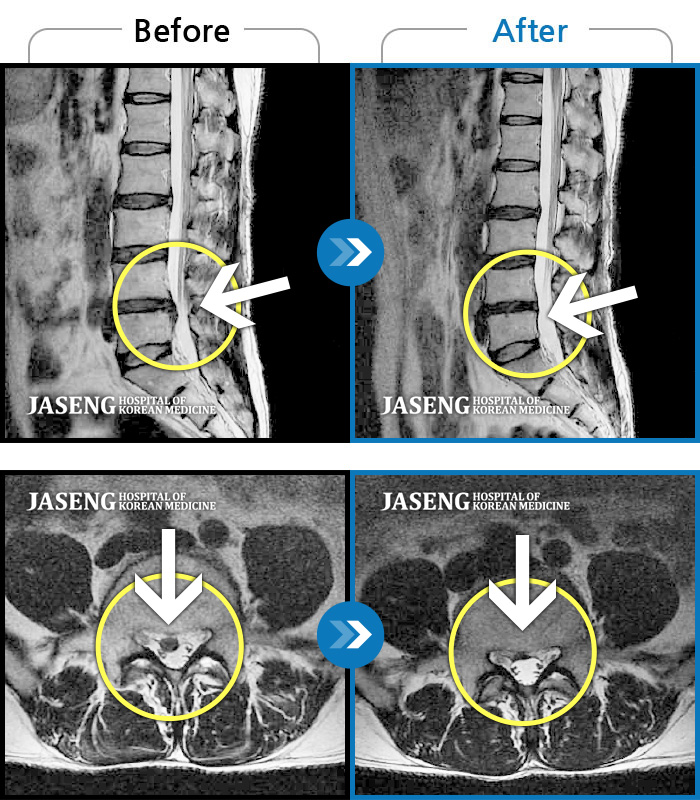

허리디스크

수원 · 김태성 원장

허리 통증과 우측 고관절~하지방사통이 심하여 활동하기 힘든 상태

촬영시기

2021.03.04 ~ 2021.10.06

2022.03.25